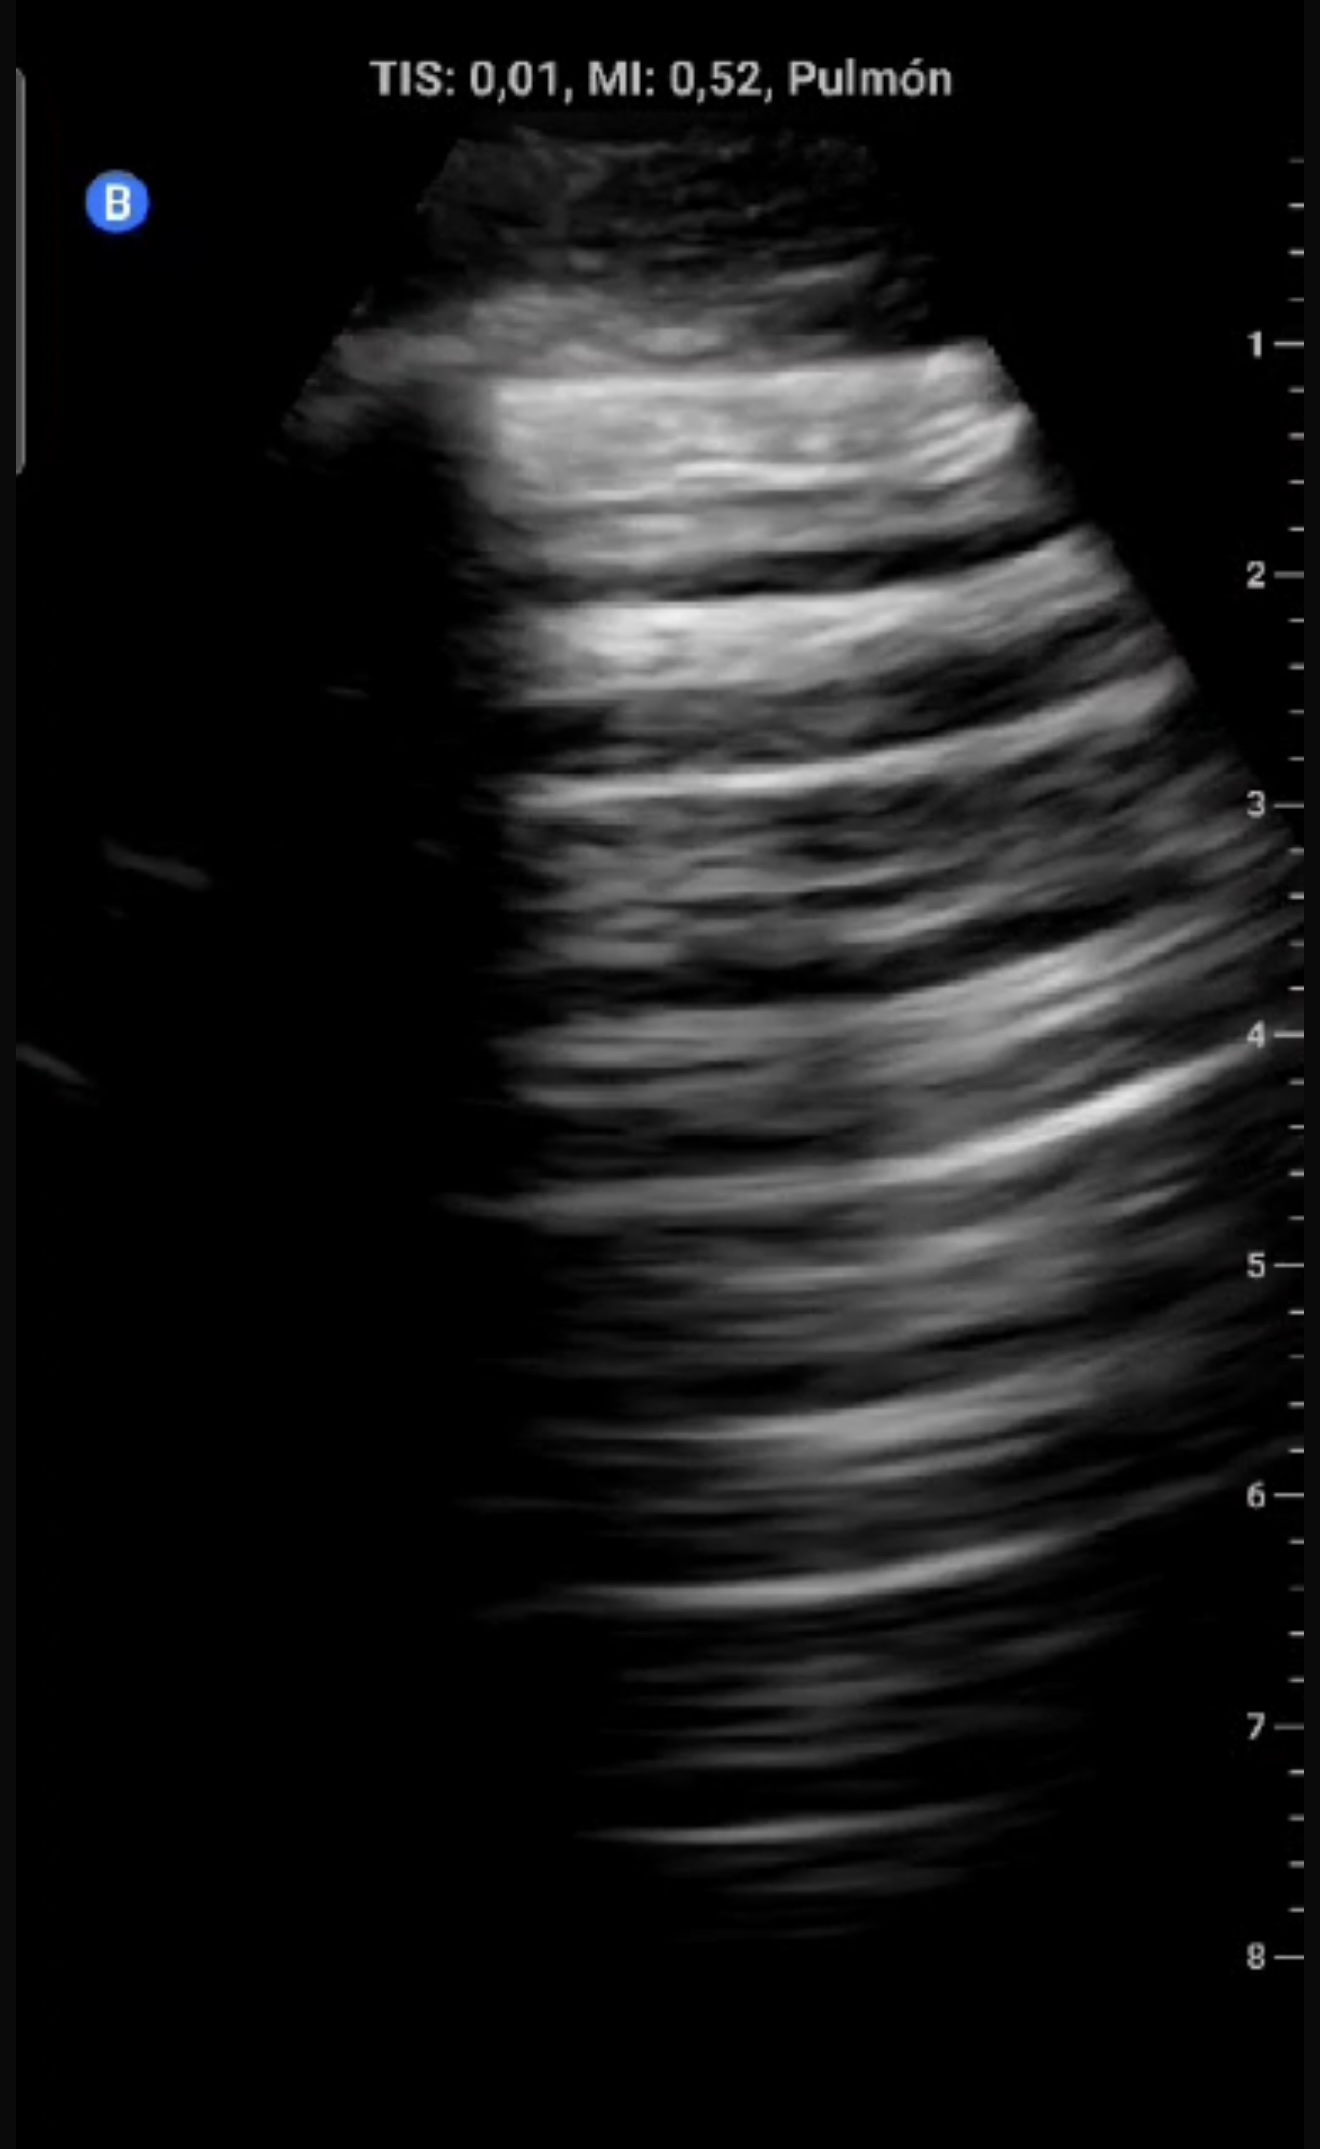

Eco clínica:

Ausencia de deslizamiento pleural (línea pleural fija), sugiriendo neumotórax.

Descripción de los hallazgos ecográficos

En modo B, ausencia de deslizamiento pleural con línea pleural estática hiperecoica. En modo M, signo de code bar (ausencia del signo de la playa).